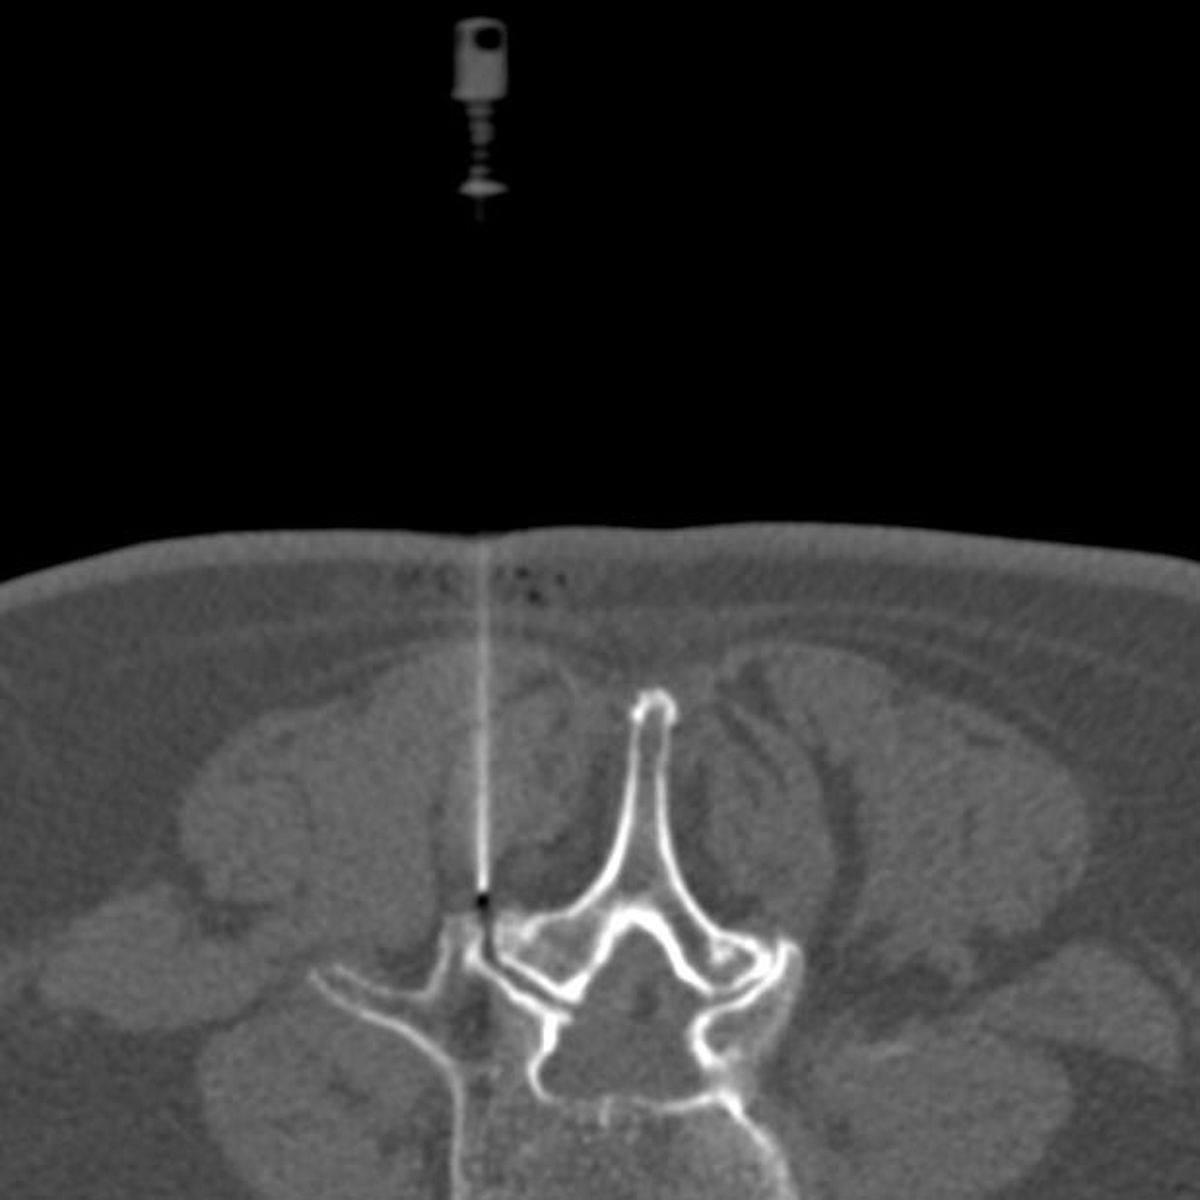

Zur Therapie stehen unsere modernen Großgeräte wie Computertomographen und Durchleuchtungsgeräte (Zwei-Ebenen-Angiographie) zur Verfügung, die schonendes und präzises Arbeiten im Millimeterbereich gewährleisten, was der Sicherheit und der Verbesserung der klinischen Ergebnisse für unsere PatientInnen dient.

- Minimalinvasive CT-gesteuerte Schmerztherapien

- Periradikuläre Therapie